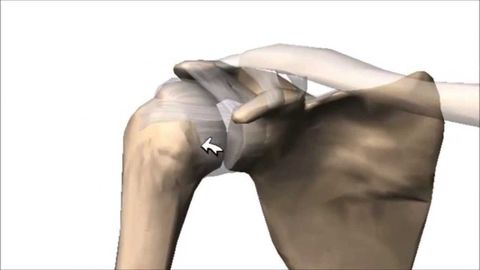

*Enartrosis: Es triaxial, movimientos en 3 planos (Sagital, coronal y transversal), forma esférica. Ejemplo: Articulación glenohumeral.